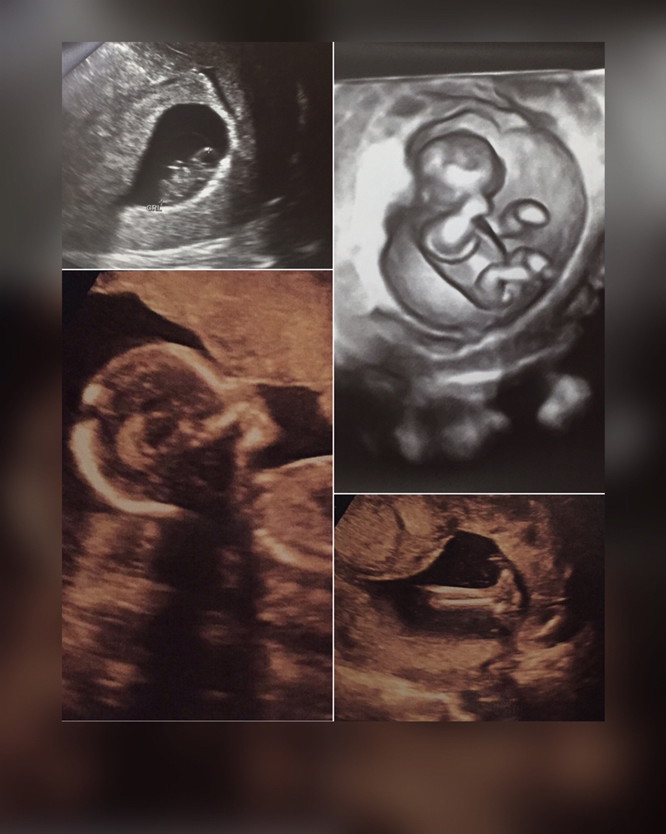

คุณหมอบอกว่าน้องเป็นผู้หญิง80%ค่ะ

ทีมธันวา..ผญ.80% เหมือนกันค่า😊😊

ธีมธันวาผู้หญิง 90% จ้า 😍